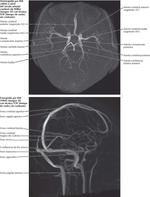

• Vasculatura cerebral